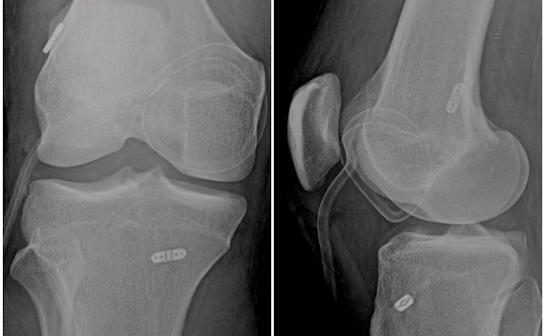

Kısmi (unikondiler) diz protezleri

Kısmi (parsiyel, unikondiler) diz protezleri, aşınmış olan diz ekleminin sadece bir kısmının protez ile yüzey kaplanmasının yapıldığı protezlerdir. Metal iki yüzey arasında plastik ara-parçadan oluşurlar. Cerrahın tercihine göre bu plastik ara parça hareketli veya sabit olabilir. Dizin iç ve dış yarısı için farklı tasarımları vardır. Eklemdeki aşınması dizin sadece sınırlı bir bölgesinde olan hastalarda unikondiler protezler tercih edilebilir.